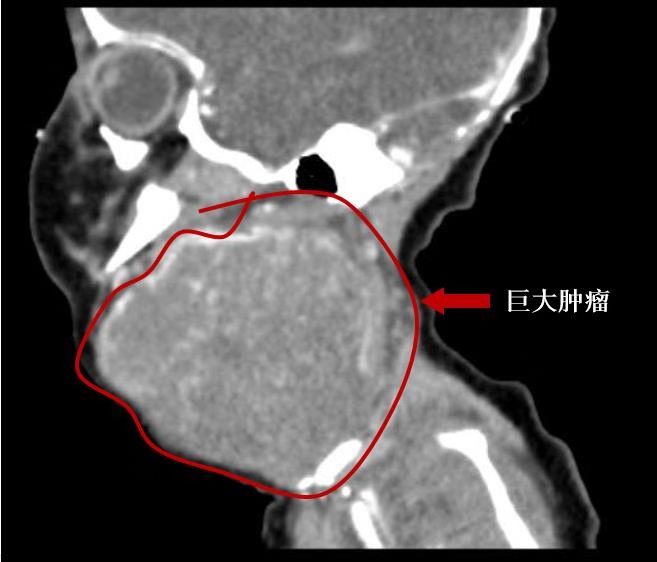

小婴出生于江苏启东,妈妈在怀孕期间常规体检未发现明显异常。两周前,小婴于当地医院顺利剖宫产。小婴的首次露面让在场的医护人员都吓出一身冷汗。原来,小婴的头颈部生长了一个与婴儿头一般大的质硬肿瘤。经当地医院影像检查显示,患儿左颈部有一个实质性肿瘤,大小约84*62*55mm。医生介绍,这个肿瘤生在颈部,严重压迫了气道,小婴出生后马上就出现了呼吸困难。

24小时后,小婴转入上海儿童医学中心新生儿科。接诊医生表示,当时发现小婴颈部的肿瘤还在快速增大,宝宝的呼吸越来越困难,已经等不及完成全部的检查和准备了。仅仅出生后96小时,小婴已经出现了严重的呼吸窘迫。